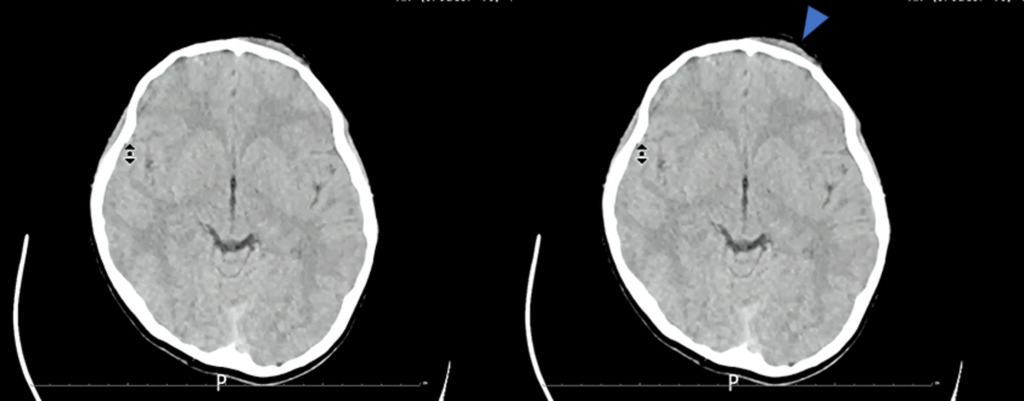

・CT画像

左前額部皮下に血腫を認めます。この辺りが受傷部と思われます。

そして翌日、再度CT検査が行われました。

翌日の頭部CTで受傷部付近の画像です。

これを見て何か気づくことはないですか?

矢印の部位でわずかにここに出血があります。

軟部条件では観察しづらいのですが、WLを50、WWを100程度に設定すると、

わずかに高吸収域を認めます。外傷後の外傷性硬膜下出血と思われます。

もう1つ高吸収域が存在しています。